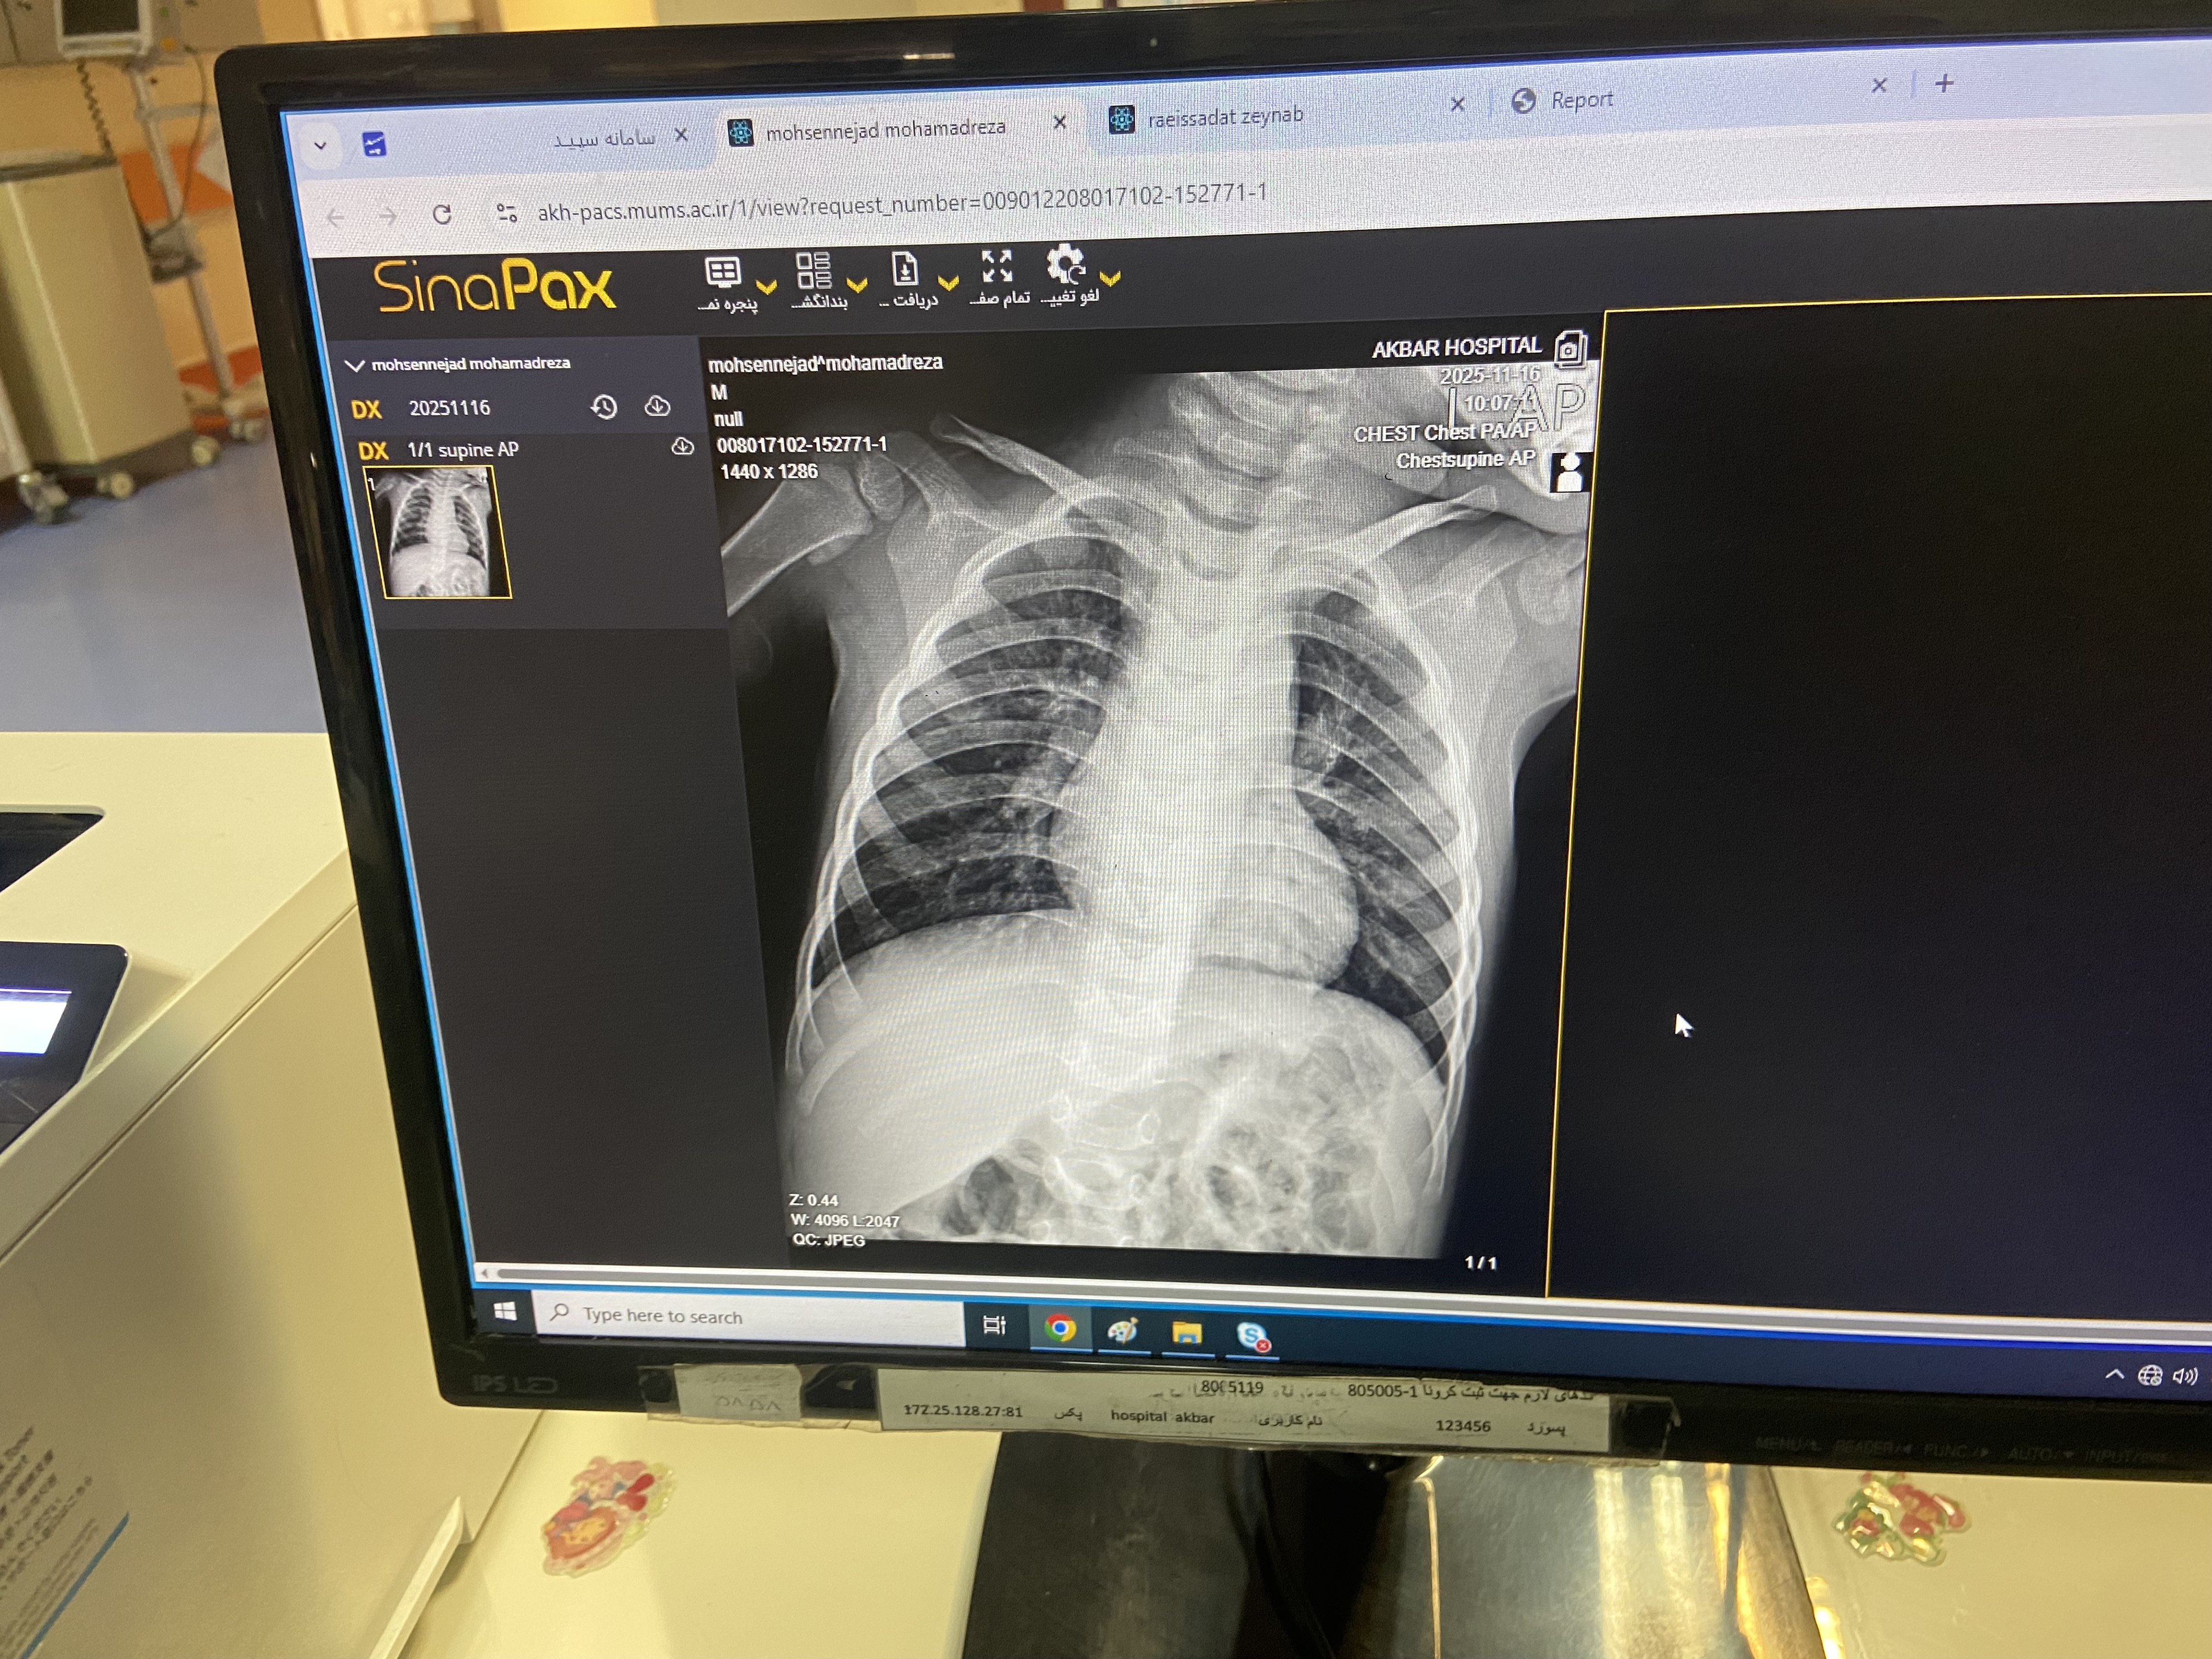

پسر 2ساله ونه ماه با تب وسرفه وابریزش و۳ بار استفراغ از دیشب به اورژانس مراجعه کرده مورد cah از ۱۷ روزگی تحت درمان با هیدروکورتیزون و فلودروکورتیزون بوده با شک به کریز ادرنال بستری شدن تاکی پنه وتاکی کاردی داشته

پنومونی

برونشیت